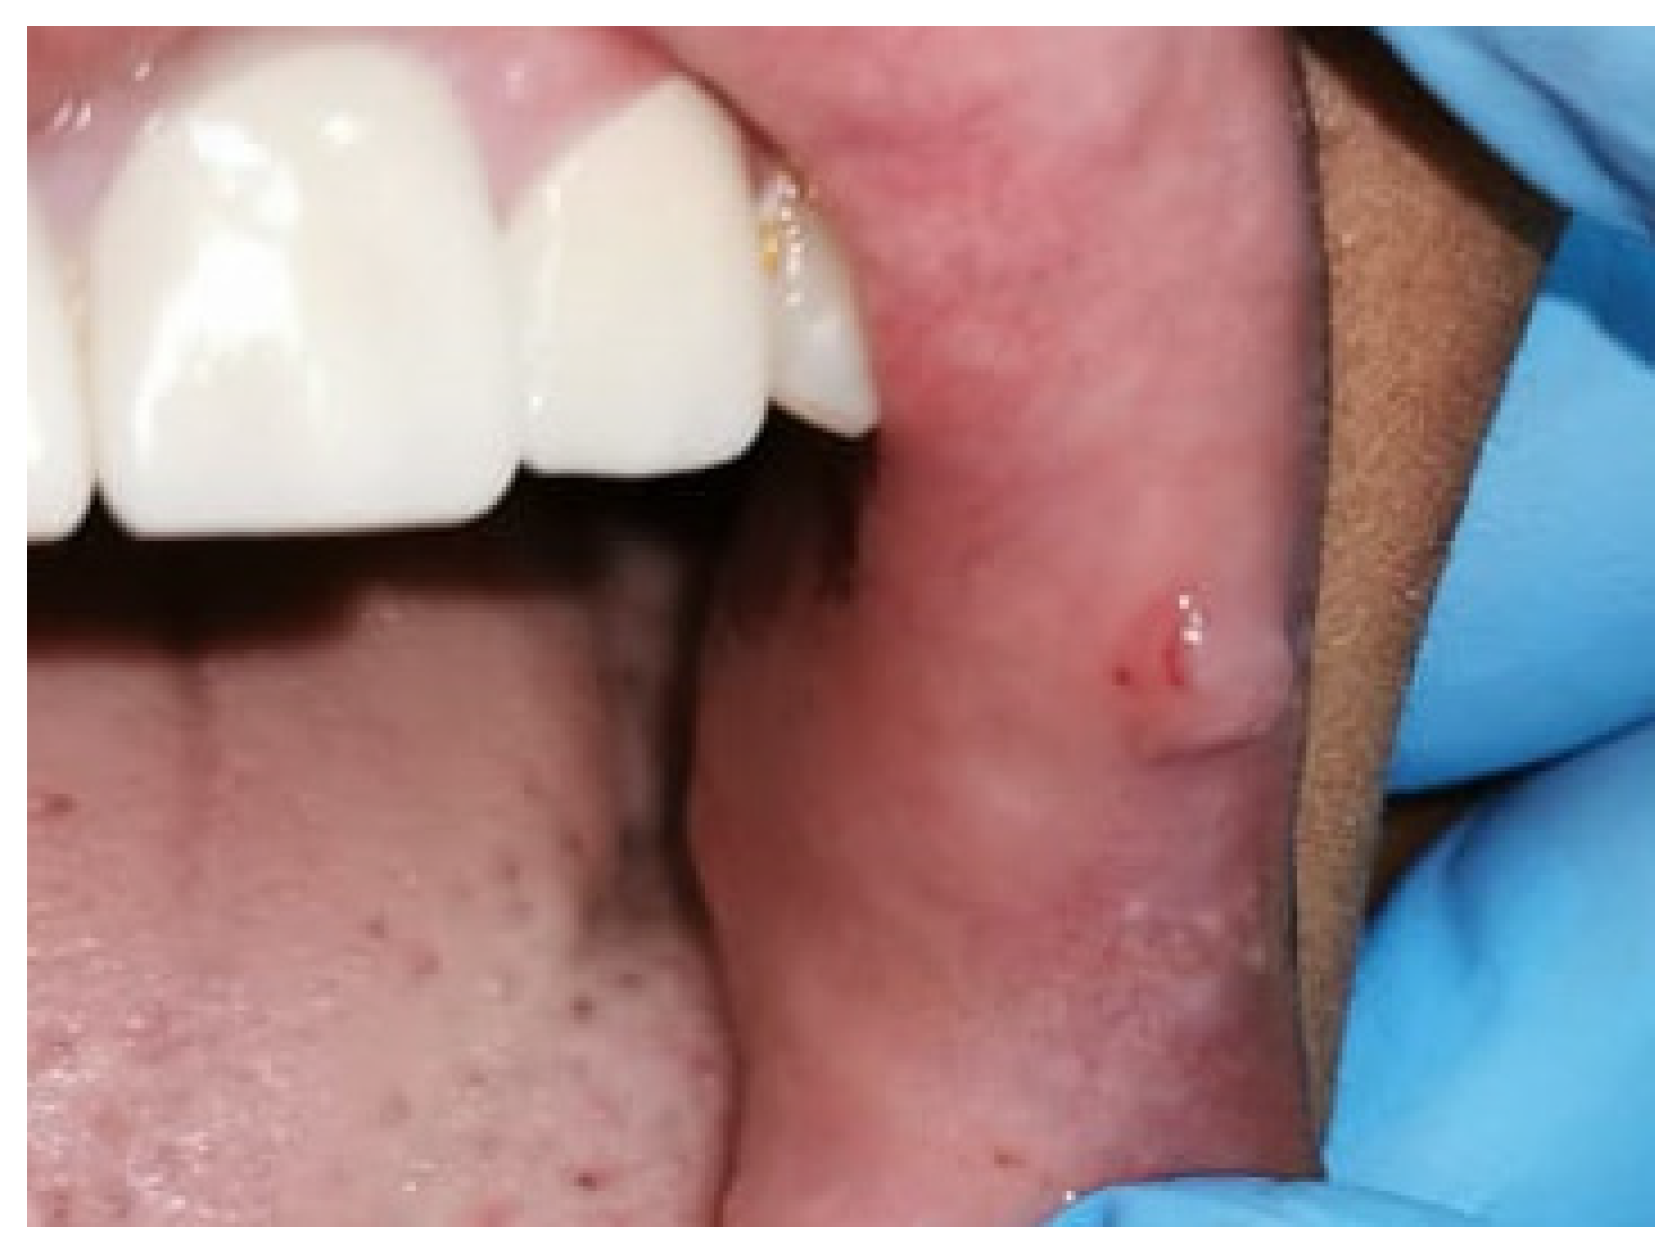

2. Case Presentation